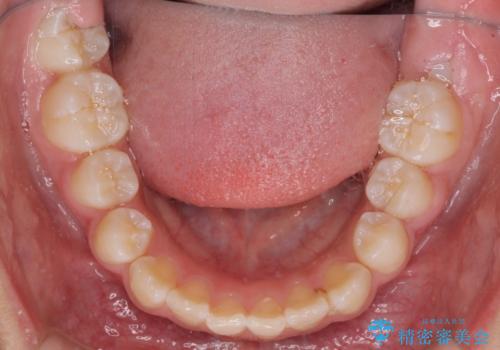

- 小学校での定期歯科検診にて歯列不正を指摘されたとのことで来院された患者様です。

左上の犬歯が低位に埋伏しており、将来八重歯になるリスクが高いと判断されたため、補助装置とワイヤーを用いて犬歯を通常の位置まで移動させることとしました。